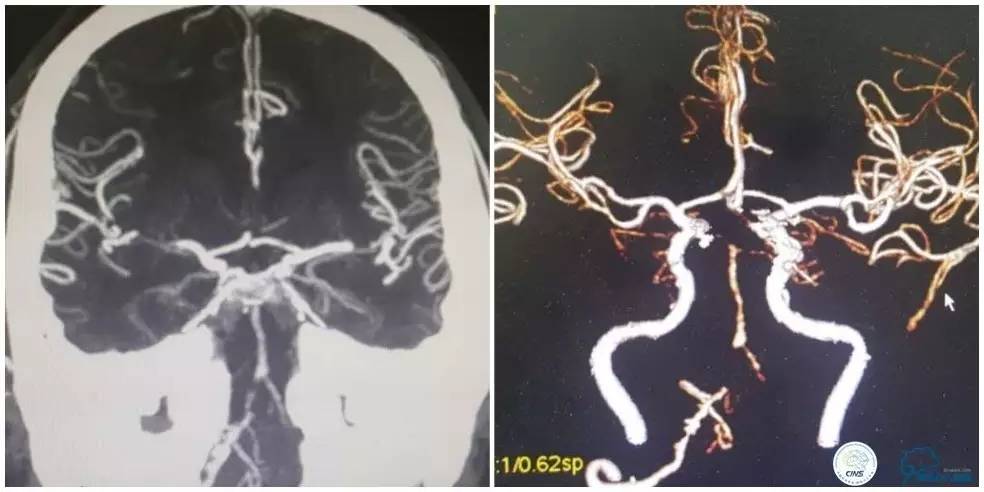

CTA:右椎动脉开口未见显影,右椎V4段钙化,右椎V4-基底动脉交界区狭窄,左椎动脉见V2段显影(图2)。

图2

CTA(图5):双侧椎动脉及基底动脉管腔可见多发斑块形成,管腔明显狭窄。双侧颈内动脉虹吸段可见多发斑块形成,管腔狭窄。

图5